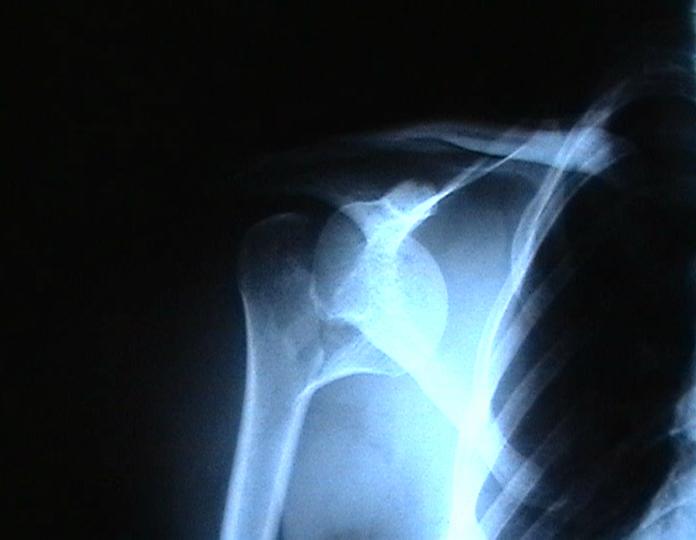

Согласен с вашим мнением -асептический некроз головки плеча. Есть ли у вас надежды на реваскуляризацию головки ? Если надеетесь, то имеет смысл продолжать физио, если нет, то следует думать опротезировании.